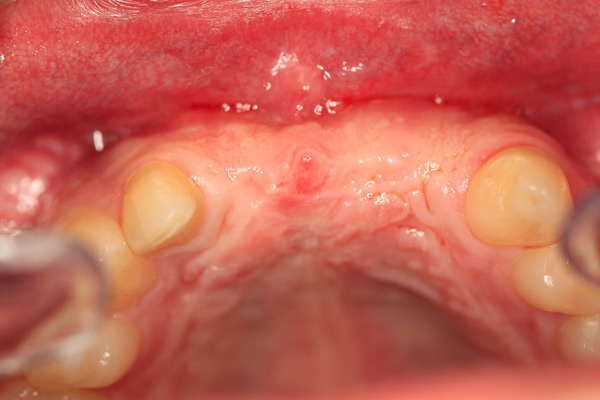

Problem: This patient presented with severe decay and a difficult occlusion/bite. He had teeth that had already been removed.

Plan: Our plan… remove the rest of the teeth and place an upper denture. Place four implants on the lower using guided surgery. Restore with a fixed/hybrid bridge.

A solution to every problem.